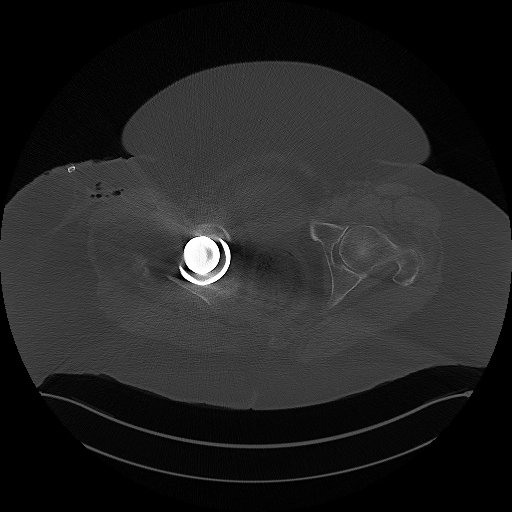

Hüft-TEP Operation rechts im Westpfalzklinikum mit CT-Kontrolle

CT Becken

DICOM

Computertomographie des Beckens (781 Bilder).

01.07.2024

780 Bilder | 512x512 px | 101 MB

781 Bilder

04.03.2025

CT-Untersuchung mit 4 Serien (853 Bilder)

CT-Untersuchung post-OP (780 Bilder)